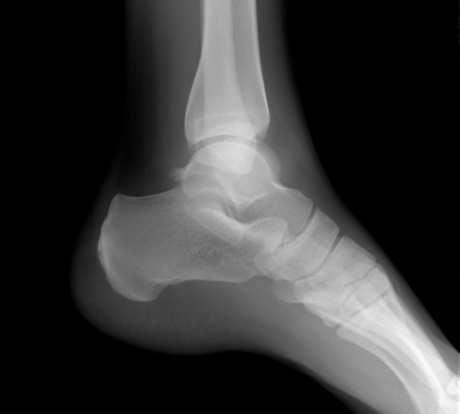

Upala tetive

Kronično stanje je prije svega rezultat neuspjelog pokušaja tijela da potpuno sanira oštećenja nastala traumom ili zbrojem mikrotrauma